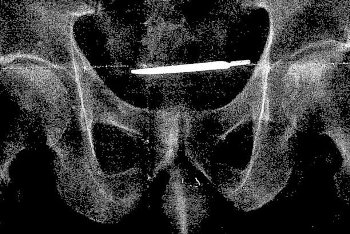

61-летний ветеран США Гленфорд Тернер из штата Коннектикут подал в суд на Министерство по делам ветеранов из-за скальпеля, который 4 года назад хирурги забыли в его теле.

Рентген показал, что в теле ветерана находится скальпель, который забыли после проведения операции в 2013 году.

В апреле 2017 мужчине сделали еще одну операцию, чтобы удалить предмет из тела.